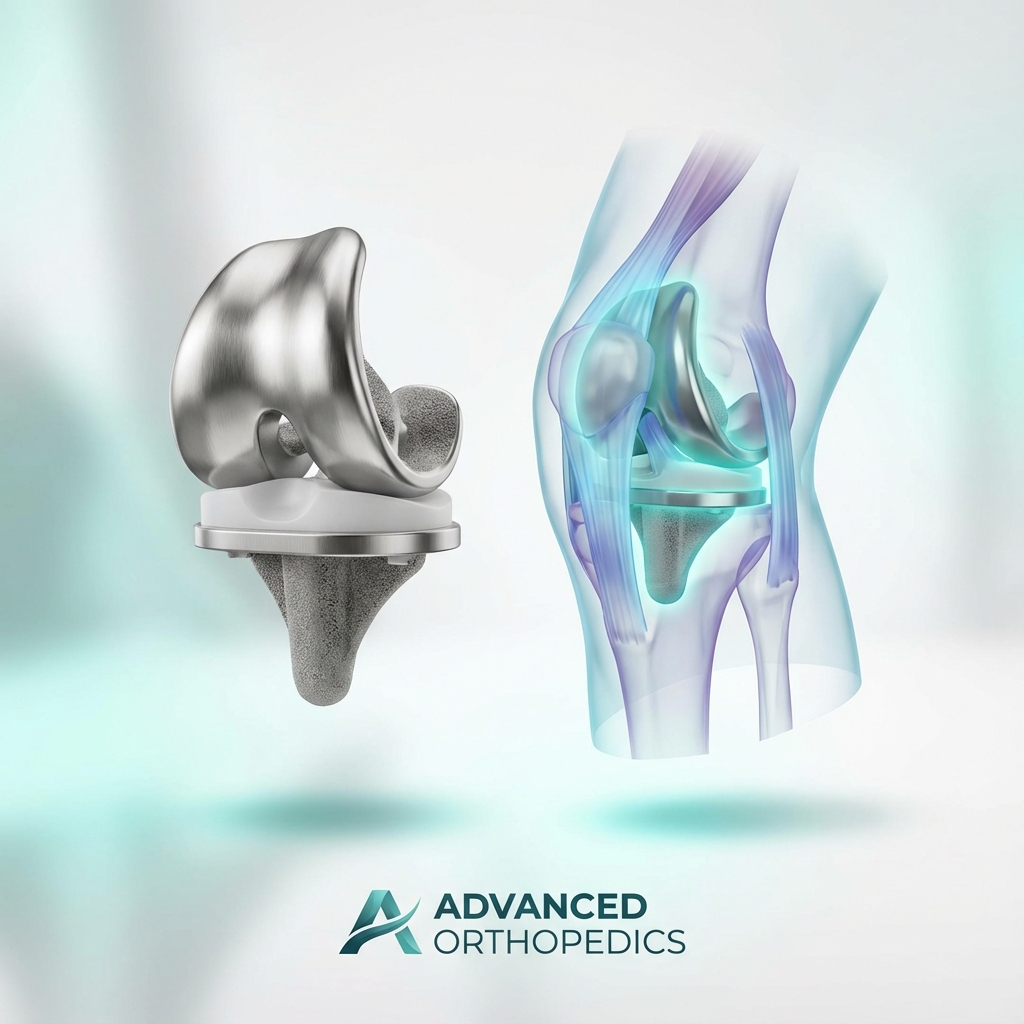

Ortopedik Travma tedavisi

Kırıklar ve kompleks ortopedik yaralanmalarda cerrahi çözümler.